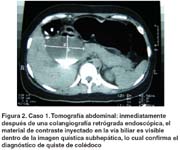

La ecografía mostró una masa quística de 7cm de diámetro en la región subhepática. La tomografía mostró una imagen quística hipodensa, redondeada, de 7x7cm, homogénea, y de pared delgada, que se extendía desde el hilio hepático hasta la cabeza del páncreas (figura 1).

En el cuarto día de hospitalización se dio término a la gestación por cesárea, con un recién nacido vivo normal. En los días siguientes el dolor disminuyó notablemente. Posteriormente se realizó una colangiografía retrógrada endoscópica (CPRE) en la que el contraste inyectado en la vía biliar no fue visible en la fluoroscopía. Inmediatamente después una nueva tomografía mostró material de contraste dentro de la imagen quística subhepática (figura 2). Se confirmó así el diagnóstico de quiste de colédoco.